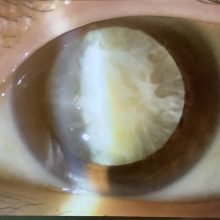

進行白内障の問題点

2024.02.24

今日は午前のみの外来で、手術の申し込みは、白内障2人、ICL1人、霰粒腫1人(49歳女性)でした。 今日、白内障の術前検査で受診された50代の女性の方は、水晶体が真っ白に濁った“成...